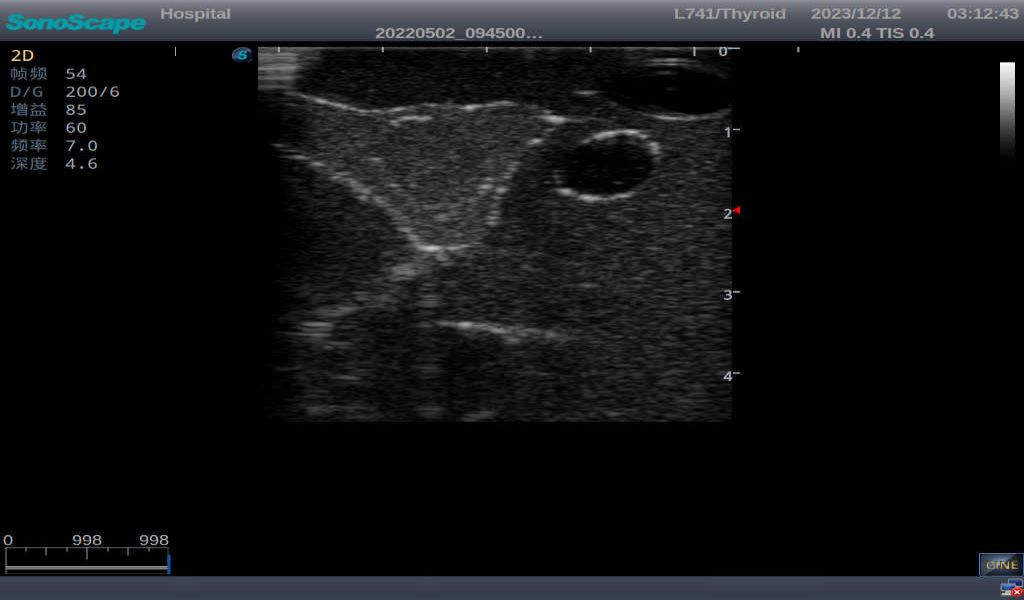

Thyroid cyst, which fluid area, dark and echo-free area can be seen